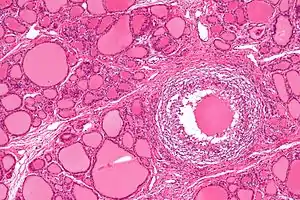

| Micrograph showing a granuloma in subacute thyroiditis. H&E stain. | |

Patients will experience a hyperthyroid period as the cellular lining of colloid spaces fails, allowing abundant colloid into the circulation, with neck pain and fever. Patients typically then become hypothyroid as the pituitary reduces TSH production and the inappropriately released colloid is depleted before resolving to euthyroid. The symptoms are those of hyperthyroidism and hypothyroidism. In addition, patients may suffer from painful dysphagia. There are multi-nucleated giant cells on histology. Thyroid antibodies can be present in some cases. The clinical presentation during the hyperthyroid phase can mimic those of Diffuse Toxic Goiter or Graves' disease. In such cases, a radionuclide thyroid uptake and scan can be helpful, since subacute thyroiditis will result in decreased isotope uptake, while Graves' disease will generally result in increased uptake. Distinguishing between these two types of disease is important, since Graves' disease and Diffuse Toxic Goiter can be treated with radioiodine therapy, but subacute thyroiditis is usually self-limited and is not treated with radioiodine.